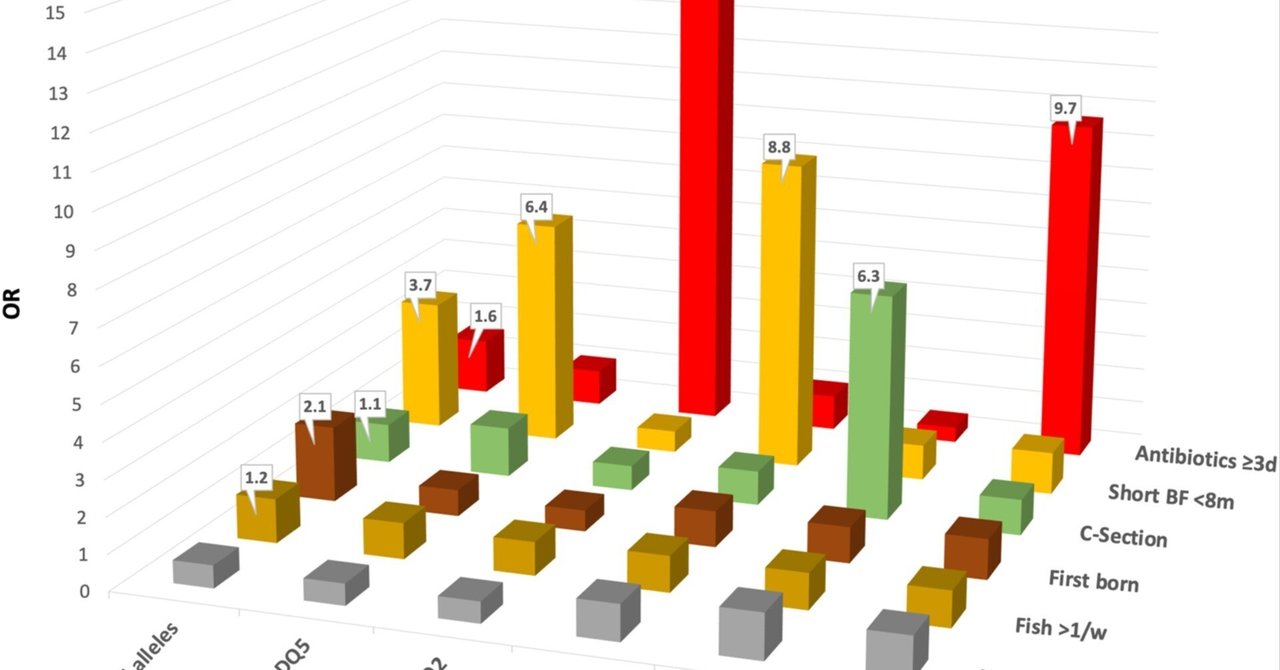

- 関節炎の付着部炎を検査するための HLA-B27 タイピング